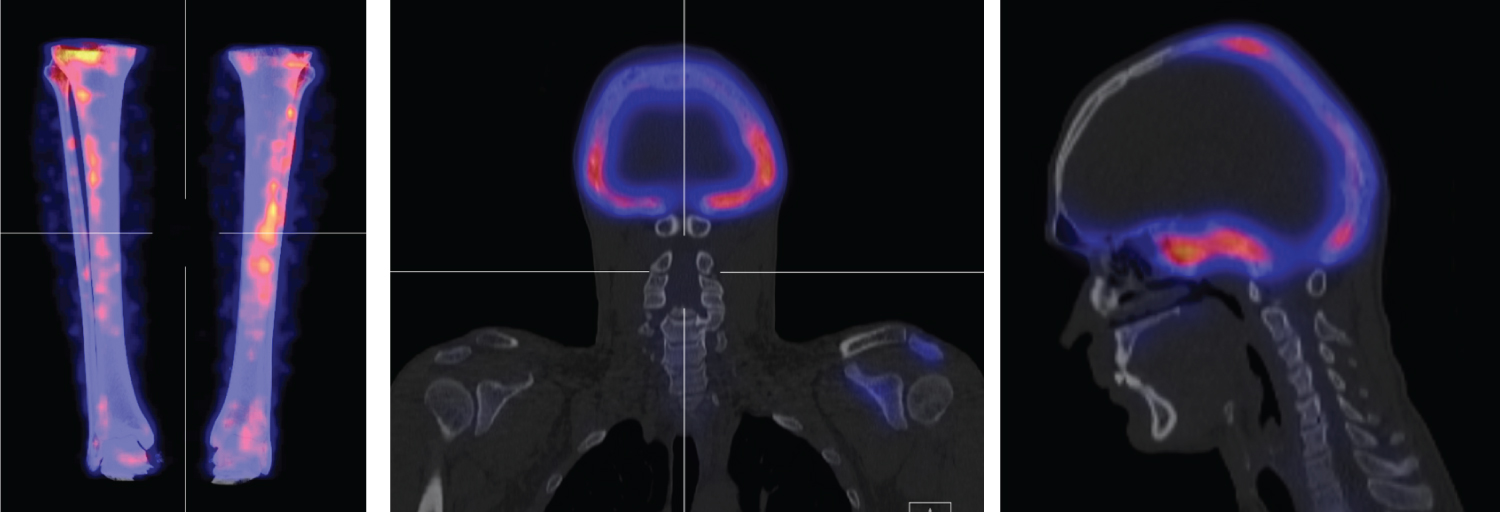

A 36-year-old gentleman was referred to our department following an incidental finding of an elevated alkaline phosphatase secondary to investigation for bone pain and vitamin-D deficiency. He initially presented with a one-year history of dull pain on the anterior surface of his left knee radiating to the tibia, with no associated stiffness or swelling. There was no history of local infection or trauma to the knee. He denied any other joint pain, previous fractures, headaches, fevers/night sweats, visual disturbances, hearing symptoms or sinus pressure. There was no history of endocrine dysfunction including precocious puberty and familial history for bone metabolic disorders was negative. No cutaneous abnormality was visible and clinical examination was unremarkable, with full range of motion of all joints. Blood tests showed a raised alkaline phosphatase of 1874 IU/L (RR 20-140), normal corrected calcium of 2.23 mg/dL (RR 2.20-2.60), with normal thyroid function tests and normal GGT (suggestive of bone origin for his raised ALP). His vitamin D was 13 nmol/L (RR > 50) and hence was started on and advised to continue Cholecalciferol replacement. His endocrine investigations and testicular USS were normal. Skeletal scintigraphy (Figure 1) evidenced areas of marked uptake in his skull, left scapula and left anterior tibia. Fusion SPECT CT imaging (Figure 2) showed changes suggestive of polyostotic fibrous dysplasia - intense activity in the skull with bony expansion of mixed lytic and sclerotic density, mild sclerosis and bony expansion in the left scapular spine and abnormal uptake in the anterior tibia bilaterally. Given the active disease in his skull and his tibial pain the patient was commenced on intravenous infusions of Pamidronate. Although no side effects were reported, unfortunately his pain did not respond well to Pamidronate. He was referred to neurosurgery due to the skull involvement evident on imaging, but due to the lack of neurological symptoms he was not a candidate for neurosurgery. The patient has made the decision to withhold from any further treatment at present and he remains under 6-monthly review.

Figure 2: Fusion SPECT CT images. Intense activity in the skull with bony expansion of mixed lytic and sclerotic density, predominantly involving the occipital bone, temporal bone and sphenoid. Mild sclerosis and bony expansion evident in the left scapular spine and acromion. Abnormal uptake in the anterior tibia bilaterally, with prominence for the left side. View Figure 2